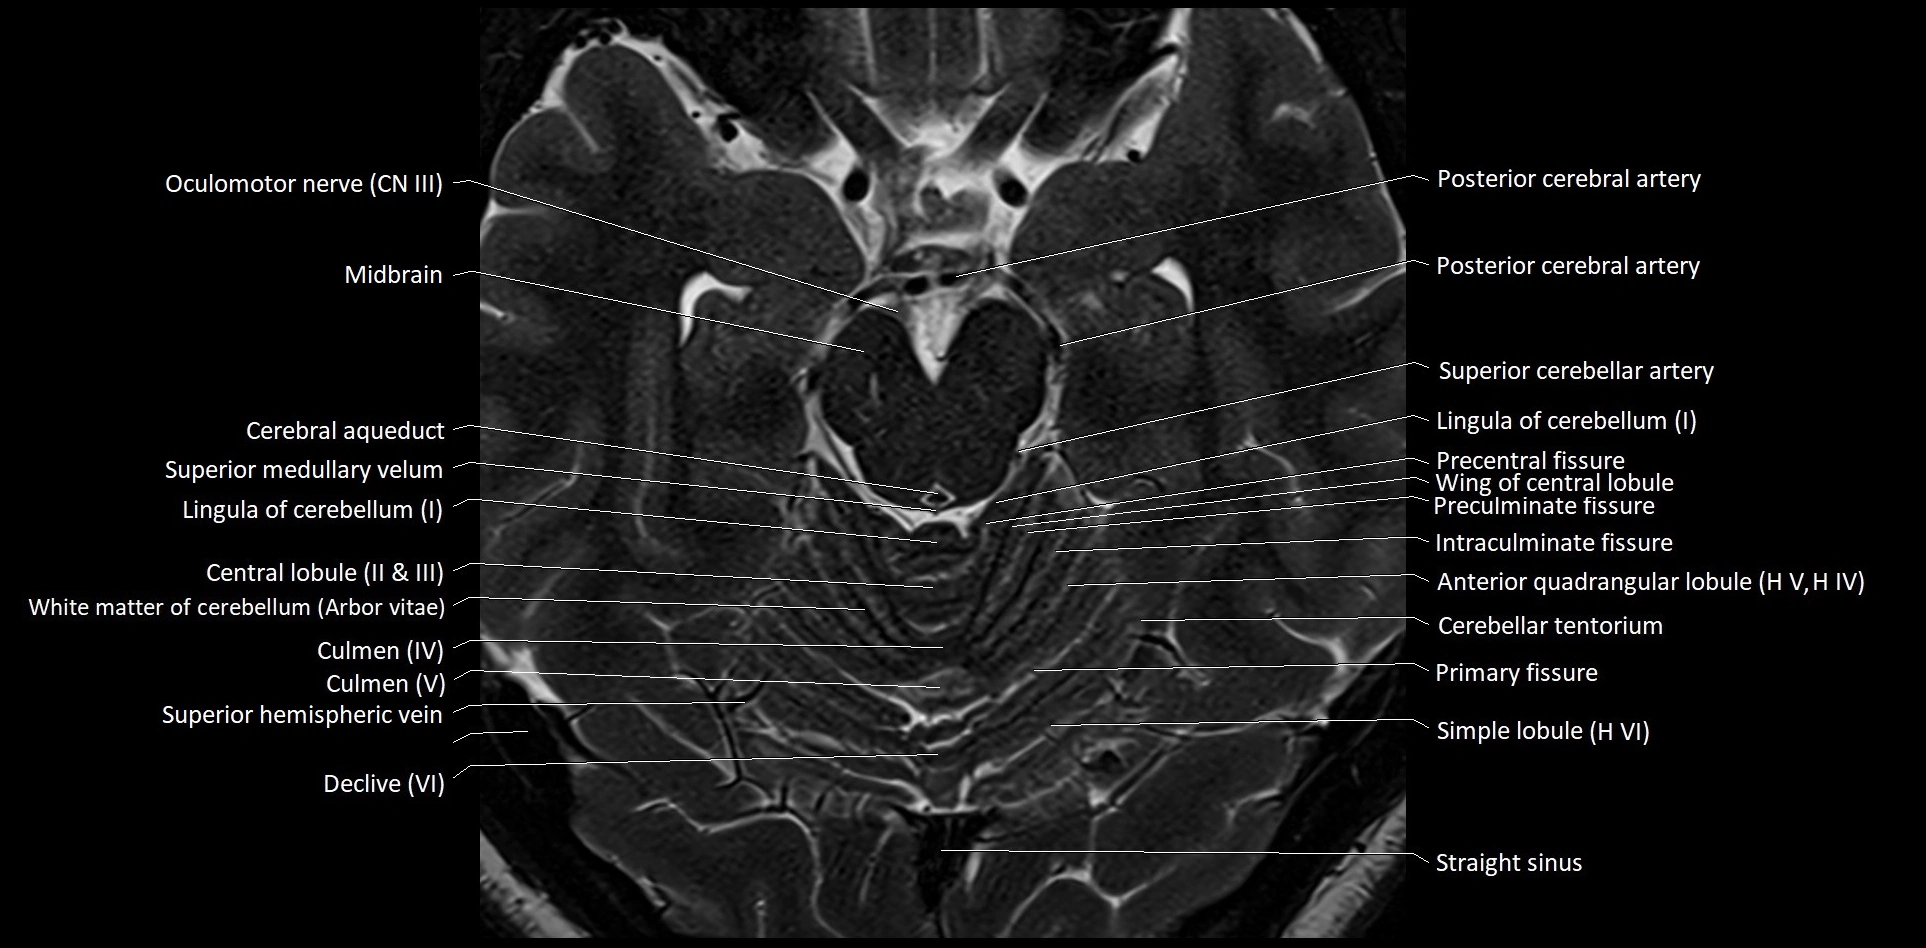

- Cerebellar tentorium

- Culmen

- Culmen (IV, V) of Cerebellum

- Declive

- Declive (VI) of Cerebellum

- Folium (VII) of Cerebellum

- Intraculminate fissure

- Lingula of cerebellum (I)

- Oculomotor Nerve (Cranial Nerve III)

- Posterior cerebral artery (P1 Segment)

- Posterior cerebral artery (P2 Segment)

- Precentral fissure

- Preculminate fissure

- Primary fissure

- Simple lobule

- Simple lobule (HVI) of cerebellum

- Straight sinus

- Superior medullary velum

- Wing of central lobule